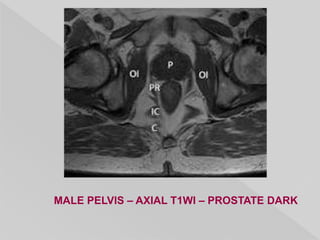

MALE PELVIS – AXIAL T1WI – PROSTATE DARK

MALE PELVIS –AXIAL T1WI – PROSTATE DARK